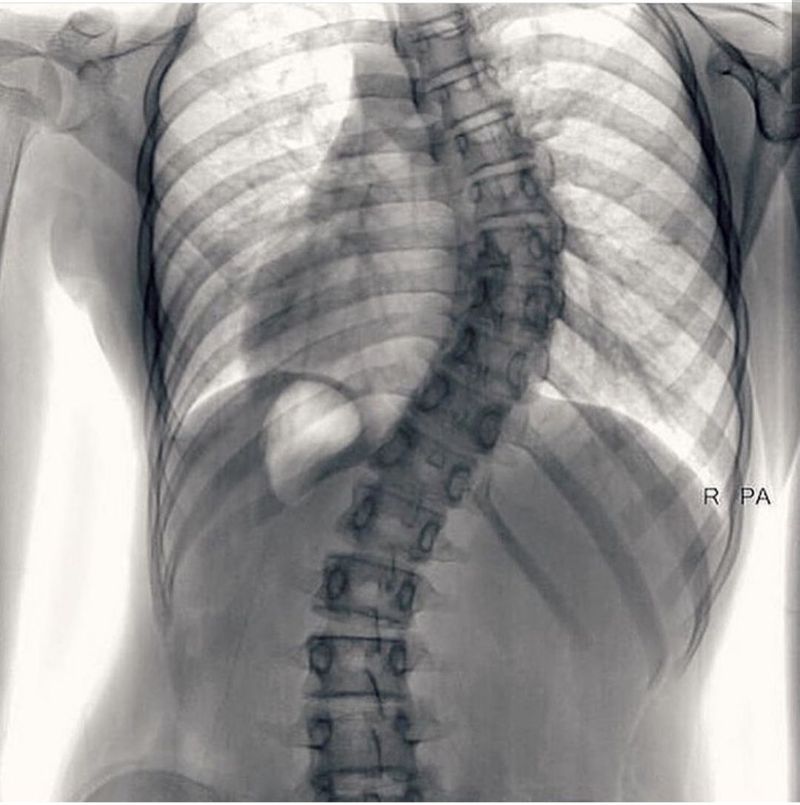

What is your diagnosis ?

Im WAYYY pre-med and at my first glance, I knew it had to be scoliosis

Scoliosis i guess